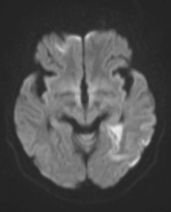

张女士被紧急送往附近医院,头颅磁共振检查明确诊断为急性脑梗死。

医生第一时间为她进行了静脉溶栓治疗 —— 这是脑梗死黄金溶栓时间窗内的常用治疗方式,可治疗后她的症状并没有明显好转。

左侧大脑中动脉和颈内动脉均已闭塞,相当于左侧大脑半球几乎断了供血,手术指征明确。